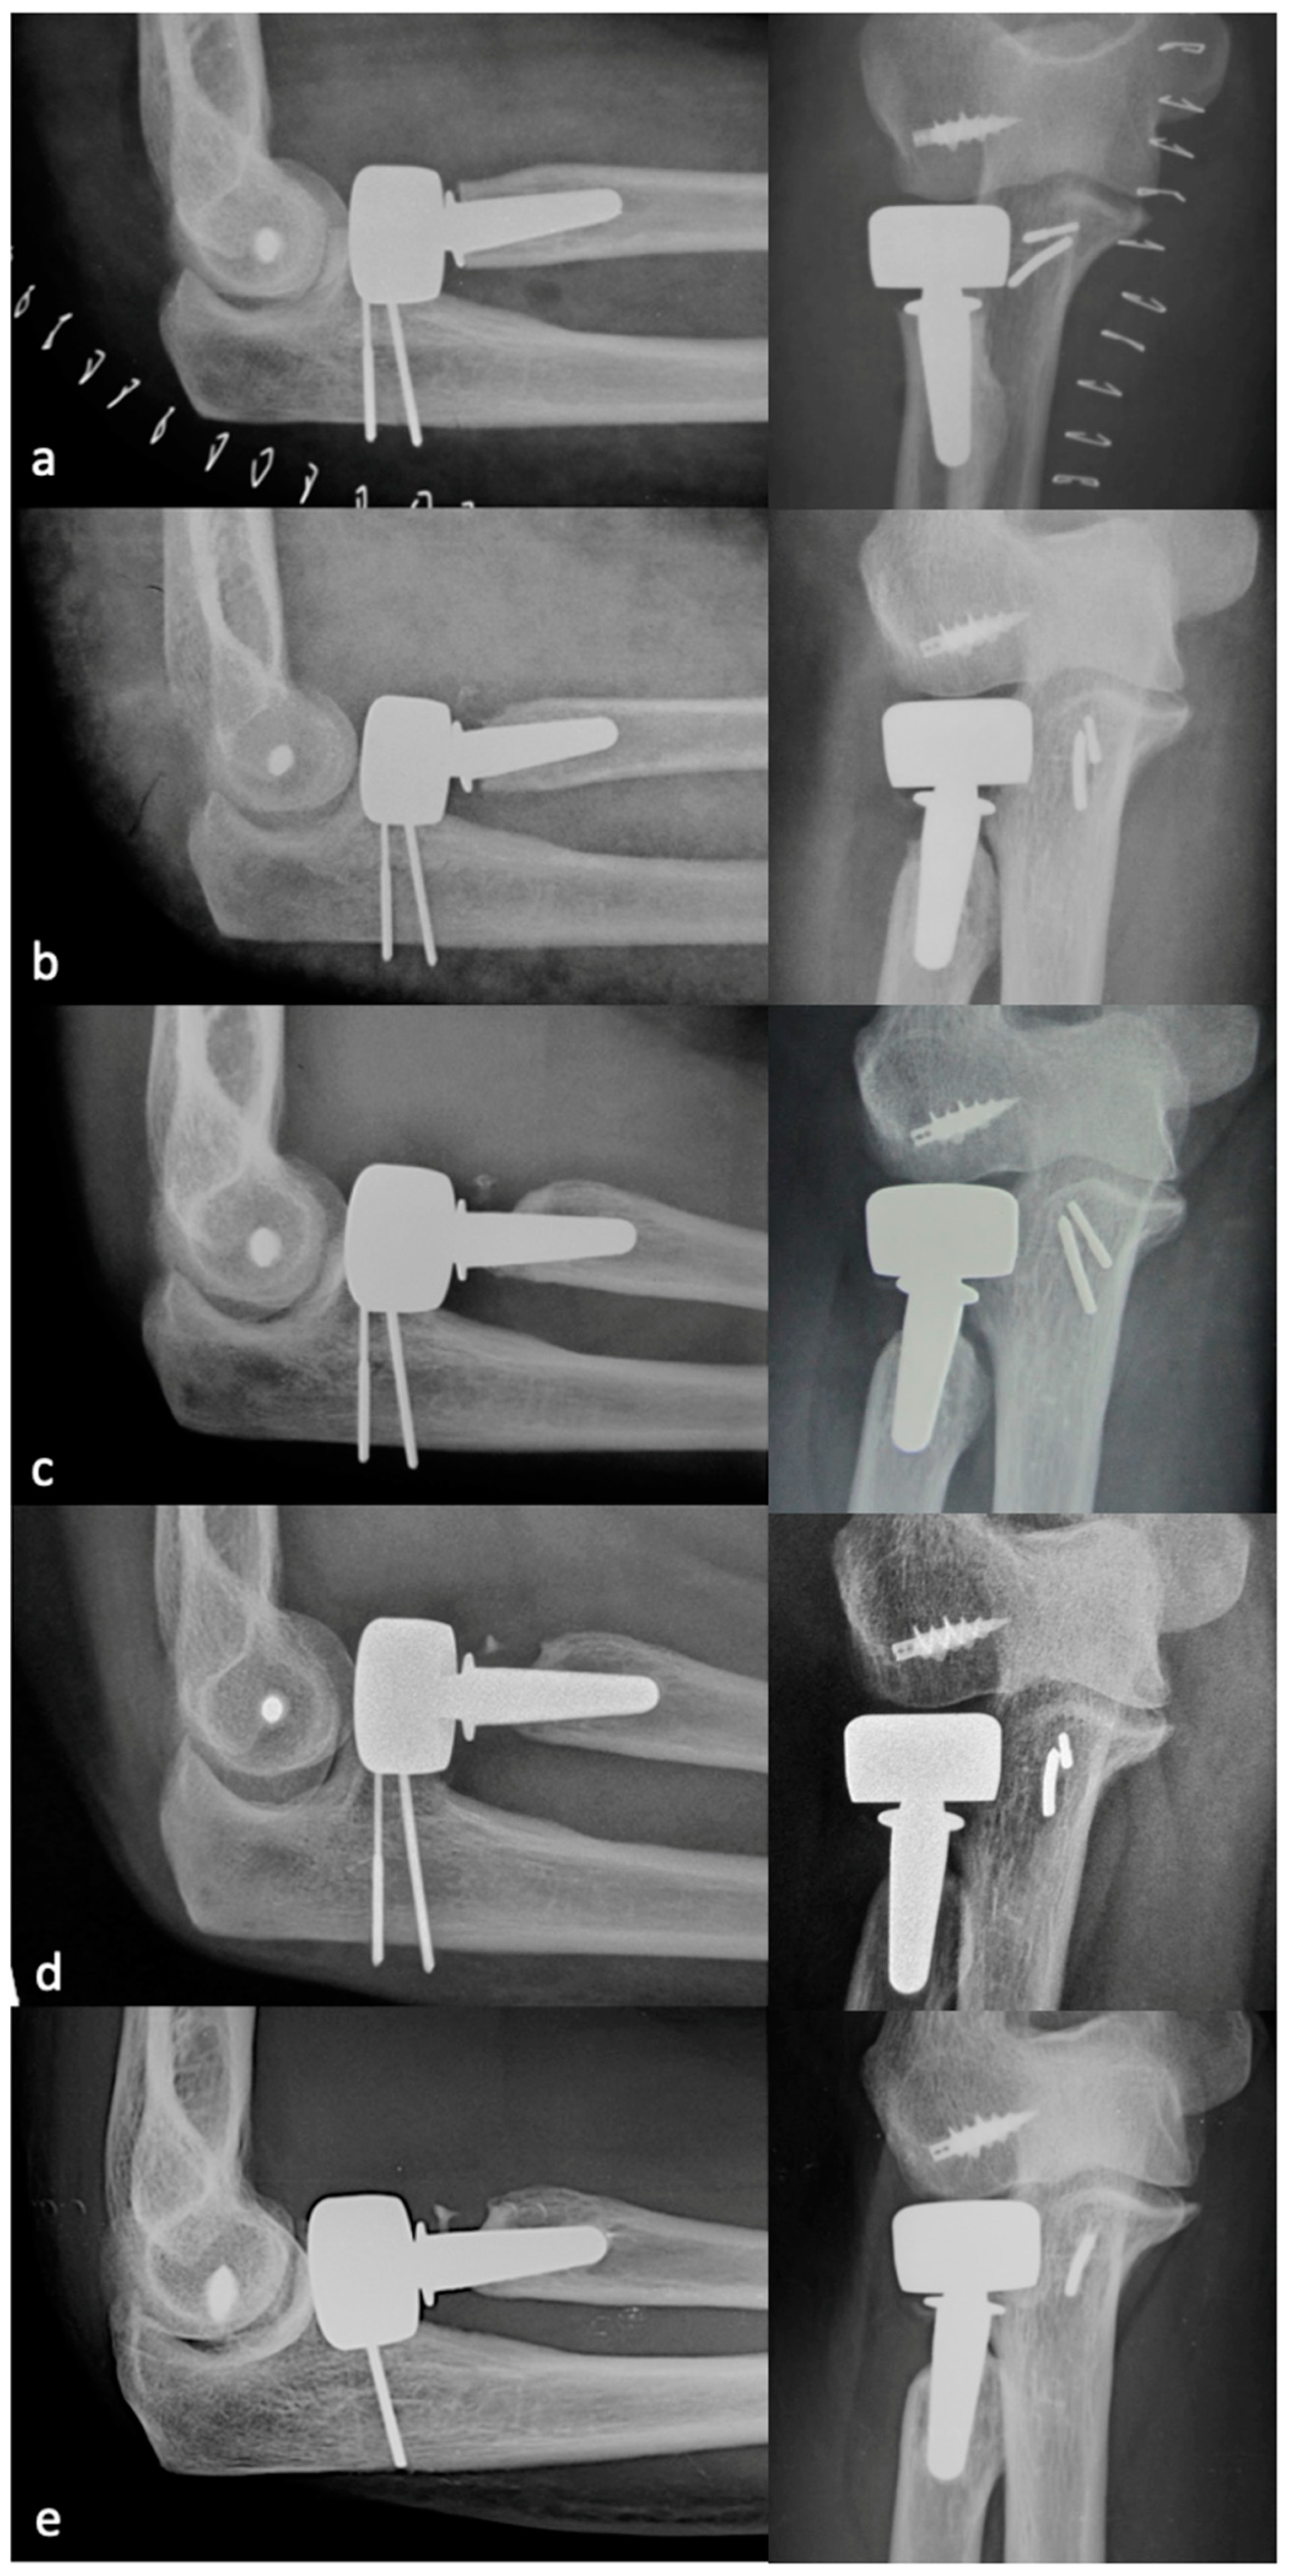

PRNR was mild in 27 patients (33%), who had an mPRNR of 1.9 mm (range: 0–2.9); PRNR was moderate in 44 patients (54%), who had an mPRNR of 4.5 mm (range: 3.1–5.9); lastly, PRNR was severe in 11 patients (13%), who had an mPRNR of 7 mm (range: 6–9.4). The typical progression of PRNR over time for an anatomical RHA is shown in Figure 3, while that for a bipolar implant is shown in Figure 4. Table 1 shows the clinical result scores in the subgroups stratified according to PRNR severity. No significant differences were observed in either the clinical characteristics or the clinical scores between the three subgroups. Indeed, no significant correlations (p = 1) (Table 2) were detected between the degree of PRNR and any of the clinical parameters in each subgroup.

Figure 4.

Progression of PRNR over time in a bipolar press-fit RHA. X-rays performed postoperatively at 2 weeks (a), 6 months (b), 1 year (c), 2 years (d), and 9 years (e). PRNR progressed until the end of the second year, while no further progression was observed beyond 2 years.